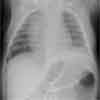

This infant required a diaphragmatic plication to facilitate weaning from mechanical ventilation. The operation was performed on the 16th day of life, and the infant was subsequently weaned from oxygen therapy. At 2-month follow-up, the infant's tachypnea and respiratory distress had completely resolved. A postoperative chest radiograph showed an improved position of the left diaphragm (Figure).